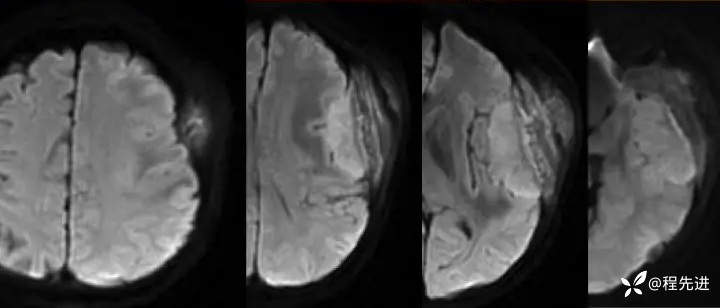

【患者信息】:女,58岁

【现病史及既往史】:发现头皮肿块,进行性增大2年余

影像检查:

1月余后: